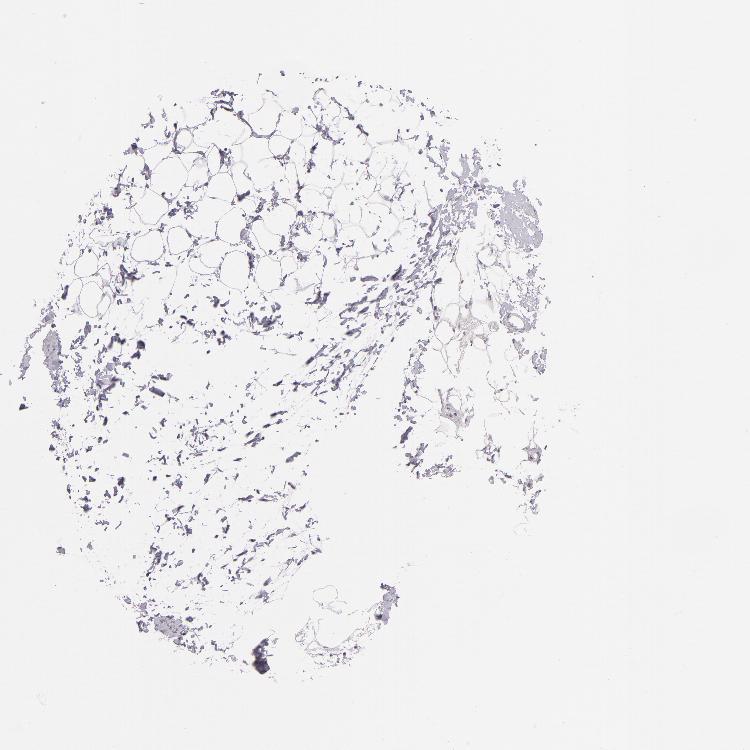

ADIPOSE TISSUE - Antibody stainingi

Antibody staining in the annotated cell types in the current human tissue is reported as not detected, low, medium, or high, based on conventional immunohistochemistry profiling in selected tissues. This score is based on the combination of the staining intensity and fraction of stained cells.

Each image is clickable and will lead to virtual microscopy that enables deeper exploration of all samples and also displays staining intensity scores, fraction scores and subcellular localization as well as patient and tissue information for each sample.

Antibody CAB001960Antibody CAB016353

Adipocytes Not detectedNot detected